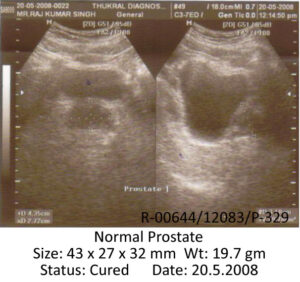

On repeat ultrasonography of prostate dated 20.5.08, the size of prostate was 43 x 27 x 32 mm and weight 19.7 gms which is normal.

Final USG prostate (20.5.08):

FINAL USG REPORT and FILM